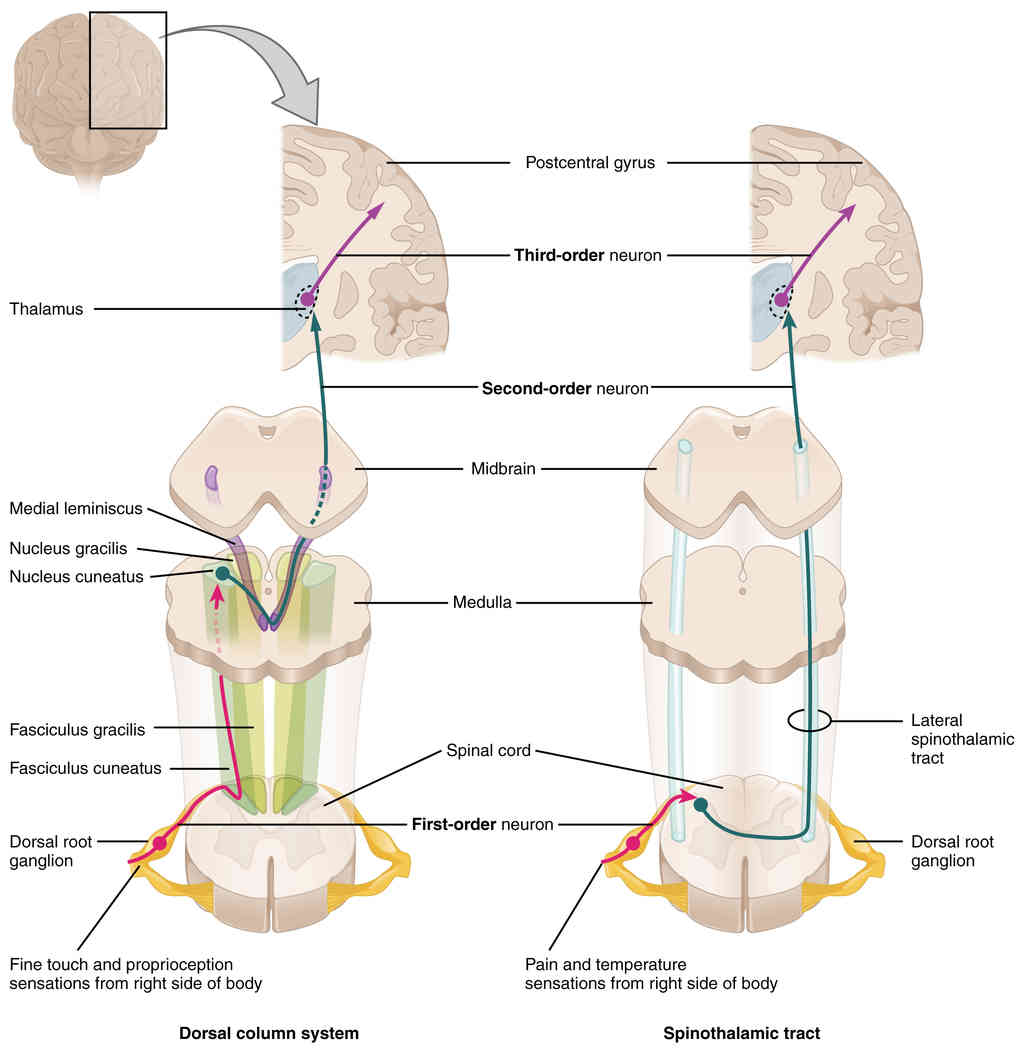

This page is under construction. For now, it is just a resource of the images found in the OpenStax Anatomy and Physiology Handbook. It wil slowly change into a revision tool. Each slide has a number. Use this to refer to the slide. When completed, it will have an unlabelled section, with labelled slides in parallel. On the unlabelled slides, write your answer and use the labelled slide to assess yourself. Keep track by also noting the number on each slide. Improvement at each attempt is important, more so than full marks on a first attempt.